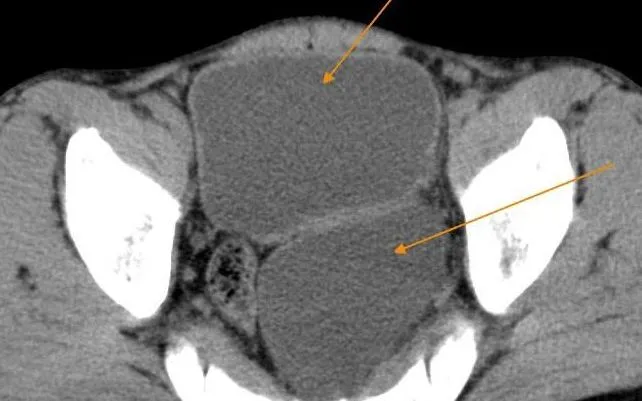

Kết quả CT-Scanner cho thấy người bệnh bị phì đại tuyến tiền liệt gây tắc nghẽn đường tiểu dưới, đồng thời có túi thừa bàng quang kích thước lớn. Túi thừa này hoạt động như một "bàng quang thứ hai", khiến dòng tiểu ứ đọng, gây tiểu khó, tiểu không hết và tăng nguy cơ viêm nhiễm đường tiết niệu. Nếu kéo dài, tình trạng này có thể ảnh hưởng đến chức năng thận.

Hình ảnh bệnh nhân có "hai bàng quang"/Ảnh BV

Người bệnh bị phì đại tuyến tiền liệt gây tắc nghẽn đường tiểu dưới, đồng thời có túi thừa bàng quang kích thước lớn. Ảnh BV